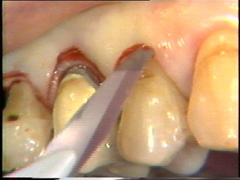

En bucal del canino la bolsa es poco profunda y aquí la incisión se ubica más cerca en de la gingiva del diente. En el lateral la insición se ubica más hacia apical de la superficie del diente.

La intención de este corte es separar los tejidos adyascentes del diente (sanos) del  tejido periodontal infectado (tejido de granulación, cemento infectado y cálculo)

En palatino debe usarse el mismo principio pero la diferencia radica que el tejido palatino es muy fibroso por lo tanto el corte puede realizarse más apical para eliminar la bolsa y poder adaptar mejor el colgajo, que por ser más fibroso es menos flexible que los colgajos bucales.